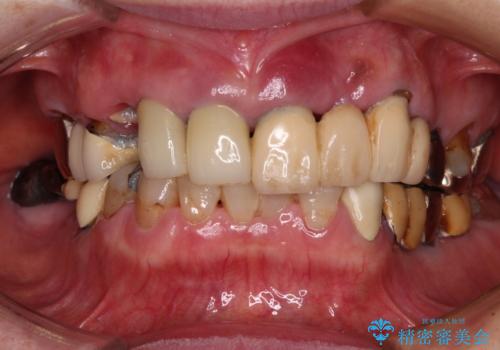

前歯をきれいにしたい インプラントや部分矯正を用いた総合歯科治療

- 抜歯の必要な前歯や、以前治療した前歯のクラウンの外観を気にして来院された患者様です。

上顎犬歯や下顎大臼歯は、必要なところはインプラントを埋入することとしました。

クラウンが不適合であったり、根管治療の必要なほどの痛みのある歯であったり、見た目の気になる前歯などをオールセラミッククラウンに補綴治療を行うこととしました。